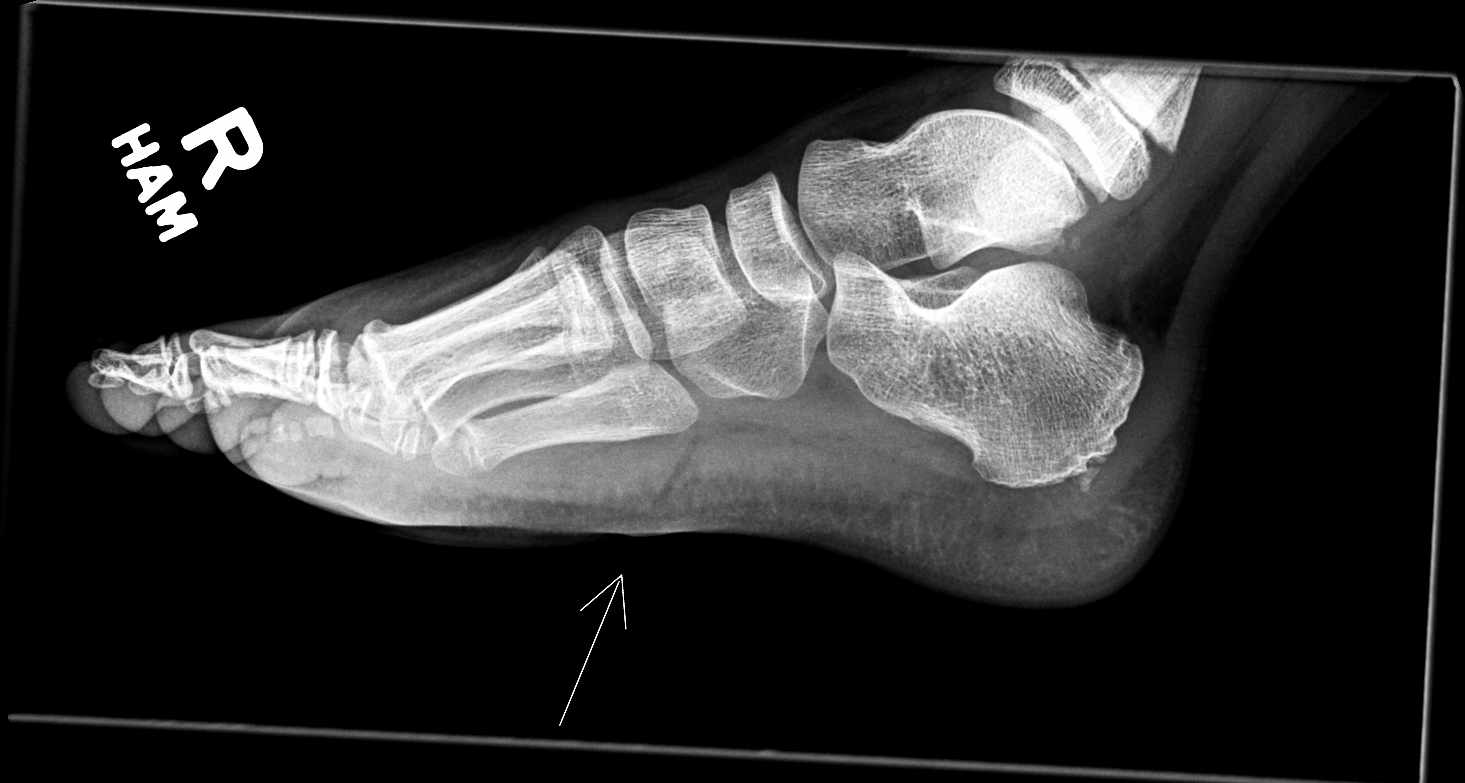

Info Images Findings Impression Reco/Acuity Case Images View Images / Launch Visage Case Notes History 2-month-old presents with decreased right arm movement, increased fussiness, and increased sleepiness for 2 days. Suspected non-accidental trauma. Exam Skeletal survey Prior Study none Dicom View Reference Material

Section 1 Submit Findings CB1550 Findings Skeletal Survey - Technique Check Skull AP/Lat Yes No Cervical and Thoracolumbar spine Yes No Chest X-Ray Yes No Ribs – Left/Right Oblique Yes No Abdominal X-Ray Yes No Pelvis with both hips Yes No Bilateral Humerus, Forearm, Hand Yes No Bilateral Femur, Tibia/fibula, feet Yes No Any additional lateral views of the extremities Yes No The exam is over or under penetrated. Yes No The exam may or may not be limited by overlying structures or soft tissues, body habitus, patient positioning, support devices, or motion. Yes No The area of concern is indicated by the patient, technologist, or care provider. Yes No The area of concern is included on the exam. Yes No Soft Tissues There is soft tissue swelling, indistinctness of fat/muscle planes, gas, or laceration in the area of clinical concern. Yes No There is an effusion, fat pad displacement, or fat fluid level. Yes No There is a radiodense or lucent foreign body. Yes No There are other densities, calcifications, post-surgical changes, or support devices in the soft tissues. Yes No Any support lines/tubes. Yes No Bone There is a break or interruption of the continuity of the cortical or cancellous bone. Yes No There is overriding of the trabeculae with apparent sclerosis. Yes No There is displacement of a fracture fragment. Yes No There is bowing of the bone in addition to the fracture at the apex of the bowed bone concerning for the greenstick. Yes No There is a spiral fracture of the leg concerning for toddler’s fracture. Yes No There is abnormal angulation or bulging of the cortical surface relative to the normal cortex which could be from a buckle or torus fracture. Yes No There is a displaced fragment which may be from avulsion by a tendon, ligament, or joint capsule or from a comminuted or other fracture. Yes No The stress trabeculae or other trabeculae of the cancellous bone are interrupted or otherwise abnormal. Yes No There is subperiosteal or endosteal reaction which could indicate a healing or subacute fracture or other abnormality. Yes No There is hard/soft callus formation. Yes No There is remodeling of the bone. Yes No There is a corner fracture or metaphyseal lesion that could be from nonaccidental trauma. Yes No There are multiple fractures of different ages. Yes No There are vertebral body/spinous process fractures. Yes No There are rib fractures. Location - posterior or lateral. Yes No There is scapular/sternal fracture. Yes No There are fractures of the digits. Yes No There are wormian bones. Yes No There are intrasutural bones. Yes No There is metaphyseal abnormality (lucencies, increased density, erosion) which may be from something other than injury such as stress, metabolic disease (e.g. rickets with loss or distortion of the zone of the provisional calcification), neoplasm (e.g. leukemia), heavy metals, inflammation, or infection. Yes No There are metaphyseal spurs. Yes No There are bony deformities involving multiple bones. Yes No The bones are gracile. Yes No There are non-healing fractures. Yes No There is/are focal or multifocal lytic/lucent, blastic/sclerotic or mixed density lesion(s) or other abnormality. Yes No Overall bone density is increased or decreased with or without thinning or thickening of the cortical or cancellous bone. Yes No Growth plates, ossification centers, apophyses The growth plate(s) is/are abnormal. Yes No There is widening of the physis from a fracture with or without displacement of the epiphysis (Salter-Harris I). Yes No There is a fracture through the physis which then extends into the metaphysis with or without angulation or displacement (S-H II). Yes No There is a fracture through the physis which then extends into the epiphysis and is intra-articular, with or without angulation or displacement (S-H III). Yes No There is a fracture through the metaphysis, physis, and epiphysis which extends into the joint space with or without angulation or displacement (S-H IV). Yes No There is narrowing of the physis from a compression fracture (S-H V). Yes No The apophysis, epicondyle, secondary ossification center, or accessory ossicle is displaced or otherwise abnormal. Yes No The ossification centers are underdeveloped. Yes No Joints and alignment There is an effusion, fat pad displacement, or fat fluid level. Yes No The epiphysis or subchondral bone is fractured, interrupted, flattened, compressed, impacted, displaced, or otherwise abnormal. Yes No There is an intra-articular loose body or chondrocalcinosis. Yes No The joint is widened, narrowed, dislocated, malaligned, or incongruent. Yes No There is pseudoarthrosis. Yes No Other findings There are developmental changes or other anatomic variants or other existing conditions that may or may not be contributing to symptoms which can or should be further evaluated non-emergently or are otherwise incidental. Yes No The remainder of the exam is abnormal for age. Yes No The lungs show focal airspace opacity. Yes No There is pneumothorax. Yes No There is organomegaly. Yes No There is intra-abdominal calcification. Yes No There is displacement of the bowel loops. Yes No There is free intraperitoneal air. Yes No The bowel loops are dilated/obstructed. Yes No There is paraspinal soft tissue abnormality. Yes No